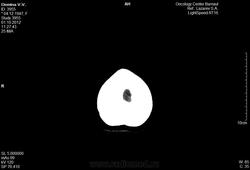

Женщина 64-х лет.

Метостаз в правой теменной кости без первичного очага.Предложена лучевая терапия. Описание снимка: форма и размеры черепа обычные, в теменной кости определяется деструкция костной ткани без четких контуров размером 16мм.

///верно ли оно?/// Признаков гидроцефалии нет никаких, непонятно на основании чего поставлен гайморит справа, киста в левой верхнечелюстной пазухе есть. По этим снимкам (в этом режиме/окне) оценить состяние костей не представляется возсожным. Скопируйтк с диска dicom-изображения, сархивируйте их, разместите на любом файлообменнике, разместите здесь ссылку. Тогда можно будет посмотреть детальнее.

По ссылкам все те же снимки. Костей нет. Дайкома тоже нет.

Наружная гидроцефалия явно надумана за счет верхних нормальных для возраста срезов, а метастаз в кости не определяется в данном окне.